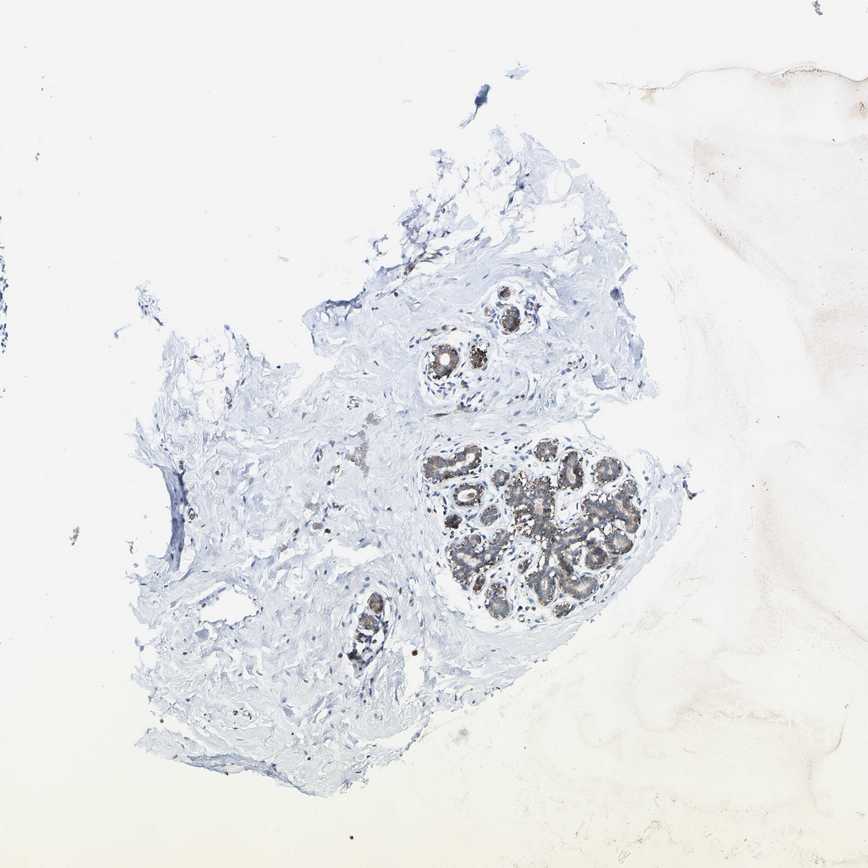

BREAST - Antibody stainingi

Antibody staining in the annotated cell types in the current human tissue is reported as not detected, low, medium, or high, based on conventional immunohistochemistry profiling in selected tissues. This score is based on the combination of the staining intensity and fraction of stained cells.

Each image is clickable and will lead to virtual microscopy that enables deeper exploration of all samples and also displays staining intensity scores, fraction scores and subcellular localization as well as patient and tissue information for each sample.

Antibody HPA016419Antibody HPA019625

Adipocytes Not detectedNot detected

Glandular cells LowMedium

Myoepithelial cells LowLow